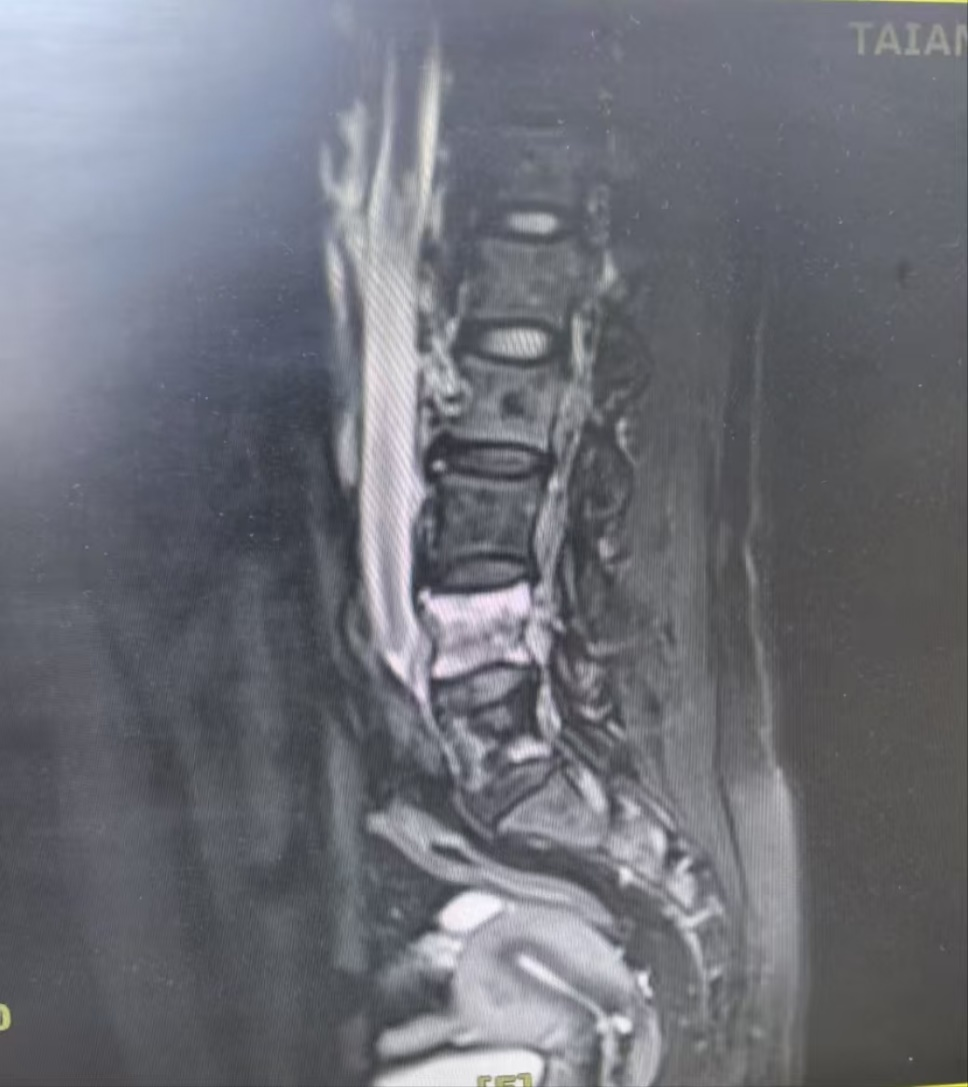

2024年4月29日-2024年6月21日,予“洛拉替尼100mg qd”口服治疗。治疗期间,肝功能及血脂异常,出现恶心、呕吐、腹泻不适,无法耐受,减量后仍无法耐受。患者出现腰痛症状,2024-06-21复查胸部+上腹部CT(图5):左肺原发灶增大,双肺新发转移灶,肝内多发转移灶,部分融合成团;查腰椎+骨盆磁共振(图6):骶尾骨、双侧髂骨、坐骨、耻骨及右侧股骨头、股骨颈骨质信号不均,见多发斑片、结节状异常信号影,T1W1、T2W1呈稍低信号,T2W1脂肪抑制序列呈高信号;子宫左侧壁见类圆形异常信号影,边界尚清,大小约5.6cm×5.7cm,T1W1呈等信号,T2W1呈高低混杂信号;所见盆腔内未见明显肿大淋巴结。

2024年6月21日至今,予“长春瑞滨软胶囊40mg/tiw 连服三周休息一周 Q4W+贝伐珠单抗 400mg d1 Q3W+地舒单抗 120mg ih Q4W”联合治疗,同时针对第四腰椎行放疗以止痛。2025-03-26,复查胸部+上腹部CT(图7):左肺原发灶缩小,双肺新发转移灶稍缩小,肝内多发转移灶较前缩小,边界清楚;颅脑磁共振:未见转移。